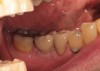

Fifteen weeks after the first procedure, the site was reopened to perform implant placement. Flap reflection revealed excellent and complete bone reformation (Figure 3). The implant osteotomy preparation was initialized with the harvest of an approximate 5-mm trephine core. The trephine had an internal diameter of 2 mm and an outer diameter of 2.7 mm. The completion of implant placement was performed according to the manufacturer's guidelines, resulting in the delivery of a 5-mm x 11-mm implant with primary stability. Because of excellent subjective stability, a transmucosal healing was chosen, with placement of a healing cap and a nonsubmerged closure (Figure 4). Qualitative histology demonstrated lamellar bone without evidence of the ACS carrier. Restorative therapy commenced approximately 4 months after implant placement. Delivery of the definitive prosthesis, consisting of a gold custom abutment and cement-retained crown, occurred at 5 months following implant placement surgery and 8.5 months after extraction and augmentation (Figure 5).

Figure 3  Re-entry demonstrating complete bone fill.

Figure 3

Figure 4  Transmucosal healing of implant No. 30.

Figure 4